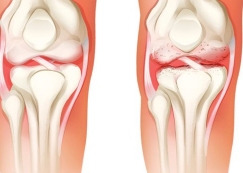

무릎통증은 일상생활에서 많이 겪는 질병 중 하나입니다. 무릎통증은 다양한 원인으로 인해 발생할 수 있습니다. 예를 들어, 연령이 들어가면서 무릎의 연골이 마모되어 발생하는 연골퇴행성 관절염, 부상으로 인한 인대 손상, 근육 부상 등이 있습니다. 이러한 무릎통증을 예방하고 치료하기 위해서는 적절한 방법을 선택하여 치료해야 합니다. 이번 글에서는 무릎통증을 예방하고 치료하기 위한 세 가지 방법을 소개하겠습니다.